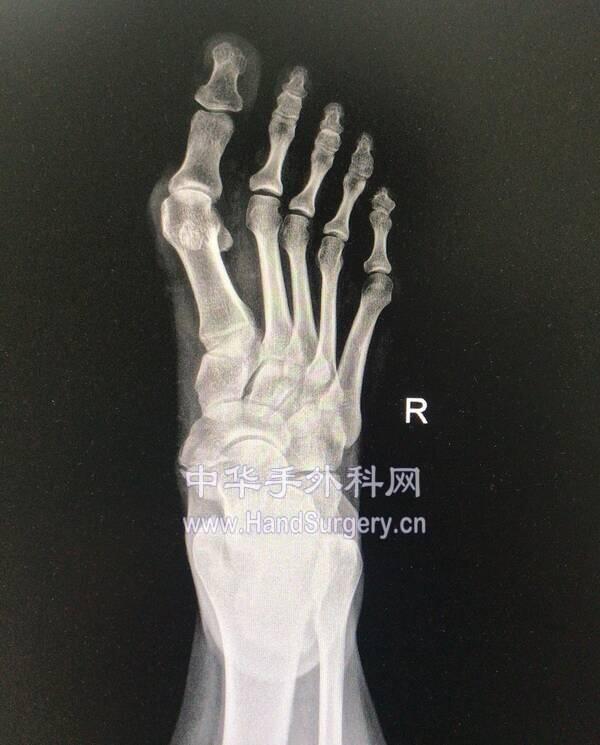

微信图片编辑_20191218175444.jpg 微信图片编辑_20191218175548.jpg

微信图片编辑_20191218175511.jpg 微信图片编辑_20191218175530.jpg

微信图片编辑_20191218175444.jpg 两侧均为中度

微信图片编辑_20191218175511.jpg